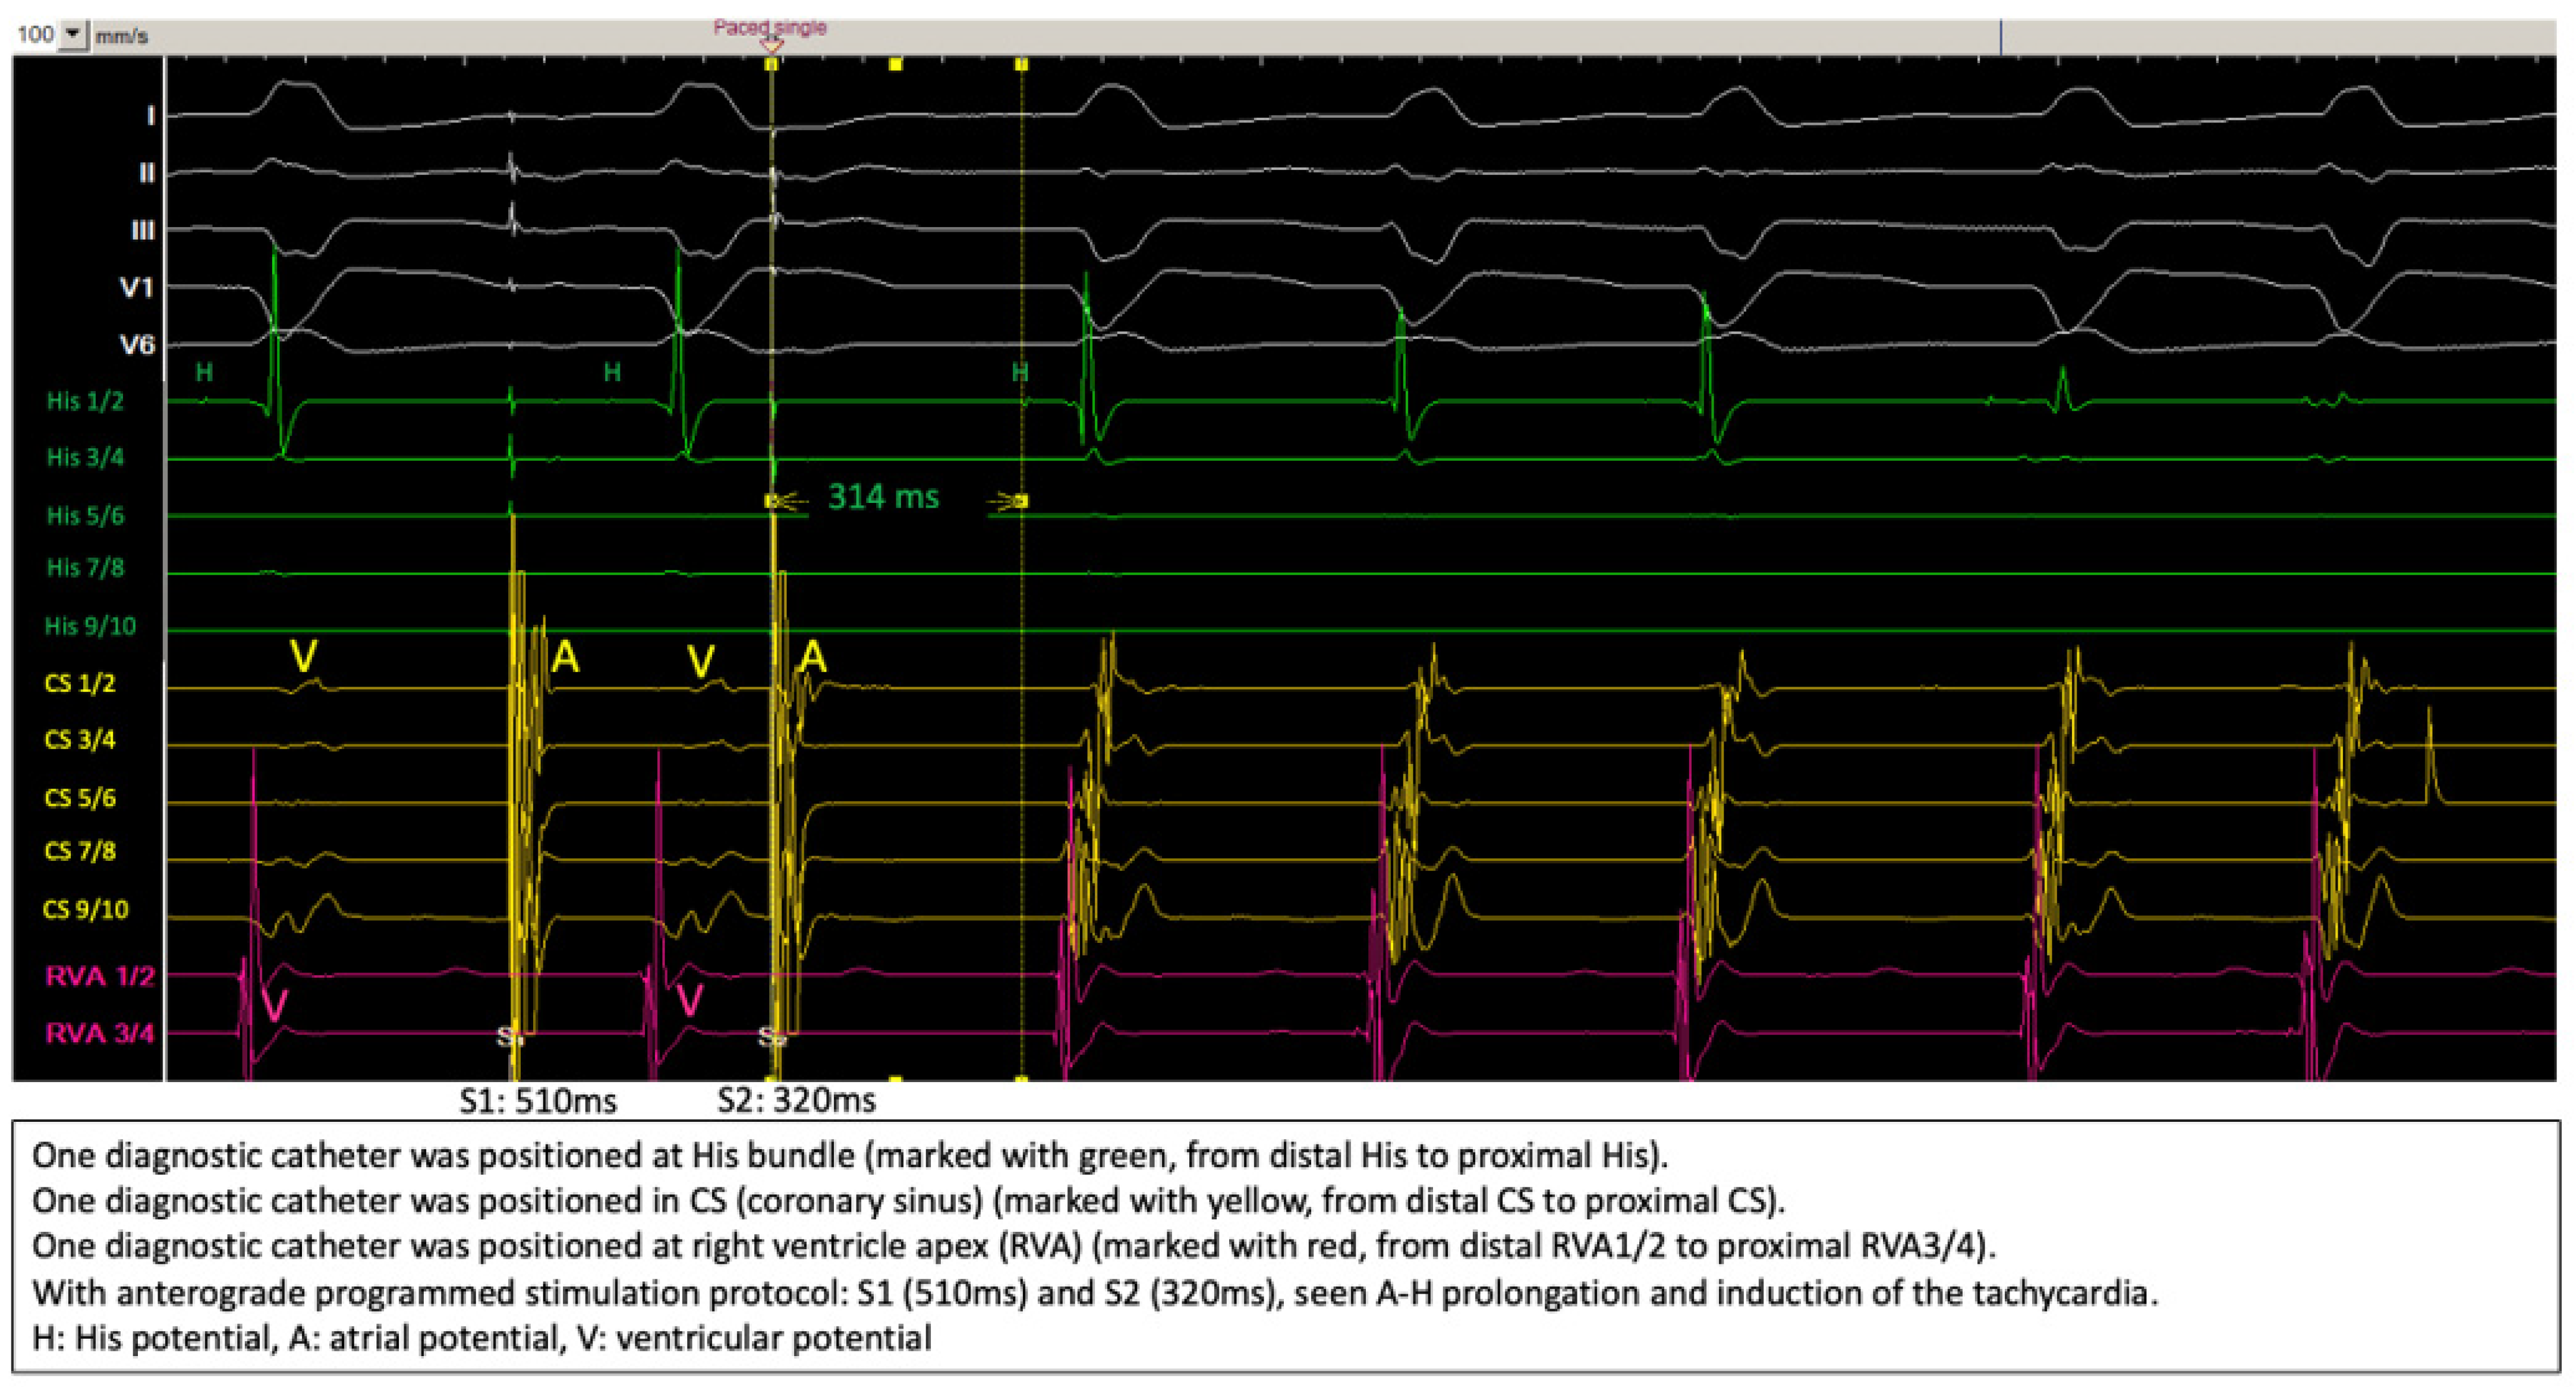

2.2. Diagnostic Workup

2.3. Ablation Strategy